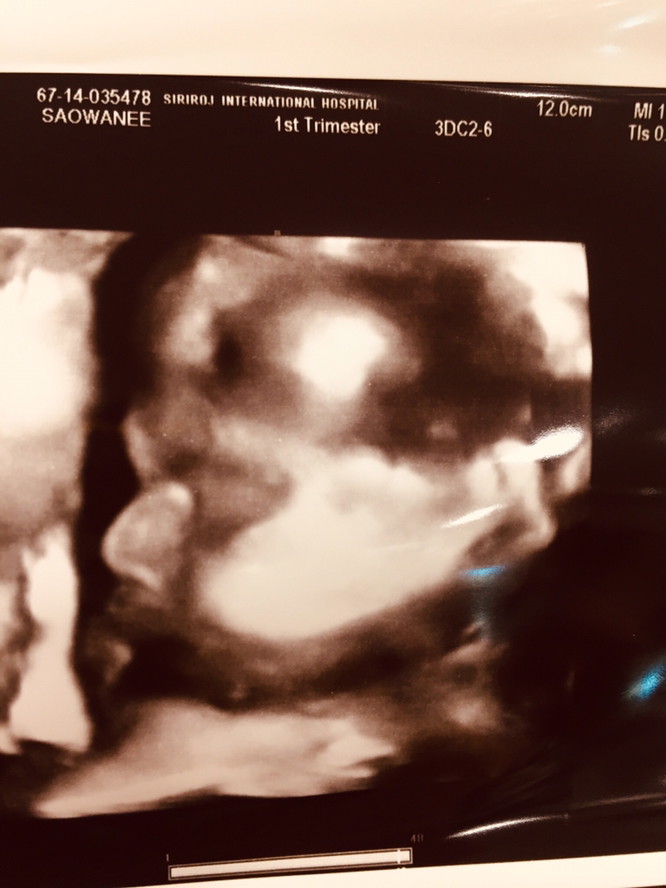

มีบ้านไหนซาวด์แล้วจมูกโด่งแบบนี้มั้ยคะ ออกมาจมูกน้องโด่งแบบนี้รึเปล่า? นี่คุณหมอบอกโด่งมาก?

แม่ซาวด์ตอนกี่วีคค่ะ โด่งมากลูก😘

ใบซาวด์ก้อโด่งค่า ตัวจริงก้อโด่ง